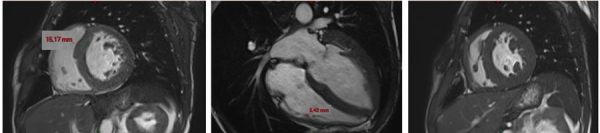

Résultats de l’IRM cardiaque:

- Fonctions systoliques bi-ventriculaires conservées avec dilatation tétra-cavitaire

- HVG concentrique (masse VG à 128 g/m2 pour une normale < 90 g/m2) avec épaisseur maximale à 15 mm en antéro-septo-basal (Figure 7)

- Hypertrophie VD avec épaisseur diastolique à 5 mm (Figure 8)

- Hypertrophie des piliers mitraux (Figure 9) et trabéculations bi-ventriculaires

Figures 7, 8 et 9 (de gauche à droite)